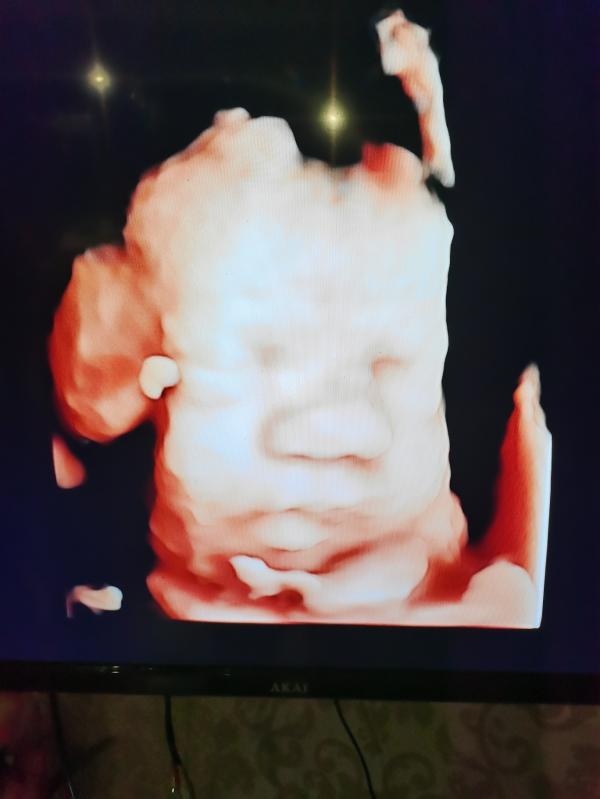

Просто оставлю это здесь, наш малыш, мы ждем тебя